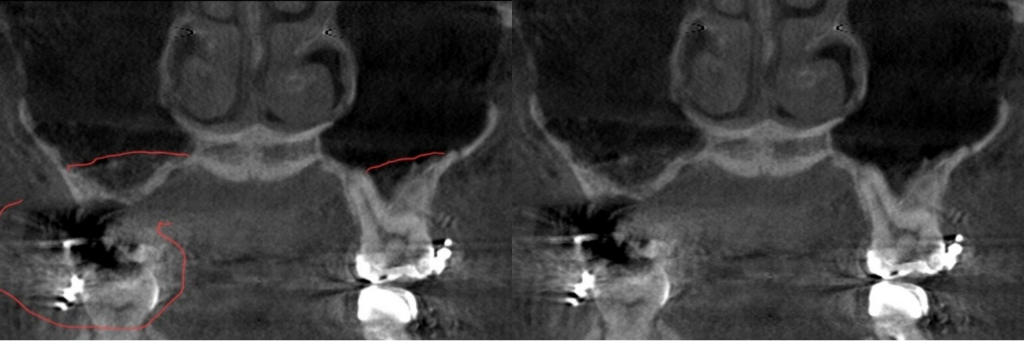

혹시 CT보면 아실수 있을까요?

부비동염인가, 상악동염인가

지금 캡쳐는 예전 ct예요, 2015년이요.

2014년에 얼굴 수술을 하면서 우측 부비동염이 크게 왔어서

마지막 CT사진상으로는 상악동염이잇을정도로 보이진 않습니다. 비염이 있으신경우 비염이 심할때 상악동에 일시적으로 염증이 생길수는 있습니다. 예전 사진으로는 상악동염은 아닌거 같습니다.

일단은 상악동염, 부비동염 정도를 일으킬 정도의 염증은 아닙니다. 만성적으로 비염이 있거나 축농증이 있을 때 정도의 염증이 있거나 일부 부위에는 염증이 없습니다. 만약에 상악동염이나 부비동염이라면 이정도가 아니라 육안으로 보더라도 확실히 염증이 보입니다. ct 사진이 과거 자료이기는 하나 과거 자료를 토대로 판단했을 때는 상악동염과 부비동염은 아닌 것으로 보여집니다.